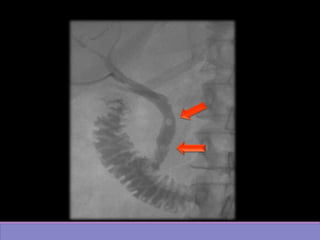

• #17 DISMINUCION DE CALIBRE DEL COLEDOCO DISTAL CON DILATACION DE LA VIA BILIAR INTRA Y EXTRAHEPÁTICA EN RELACIÓN A EDEMA DE PAPILA O A ESPASMO DE ESFINTER DE ODDI.

• #18 Imagen por fluoroscopia evidencia imagen radiolucides de via biliar con dilatación de via intra y extra hepatica